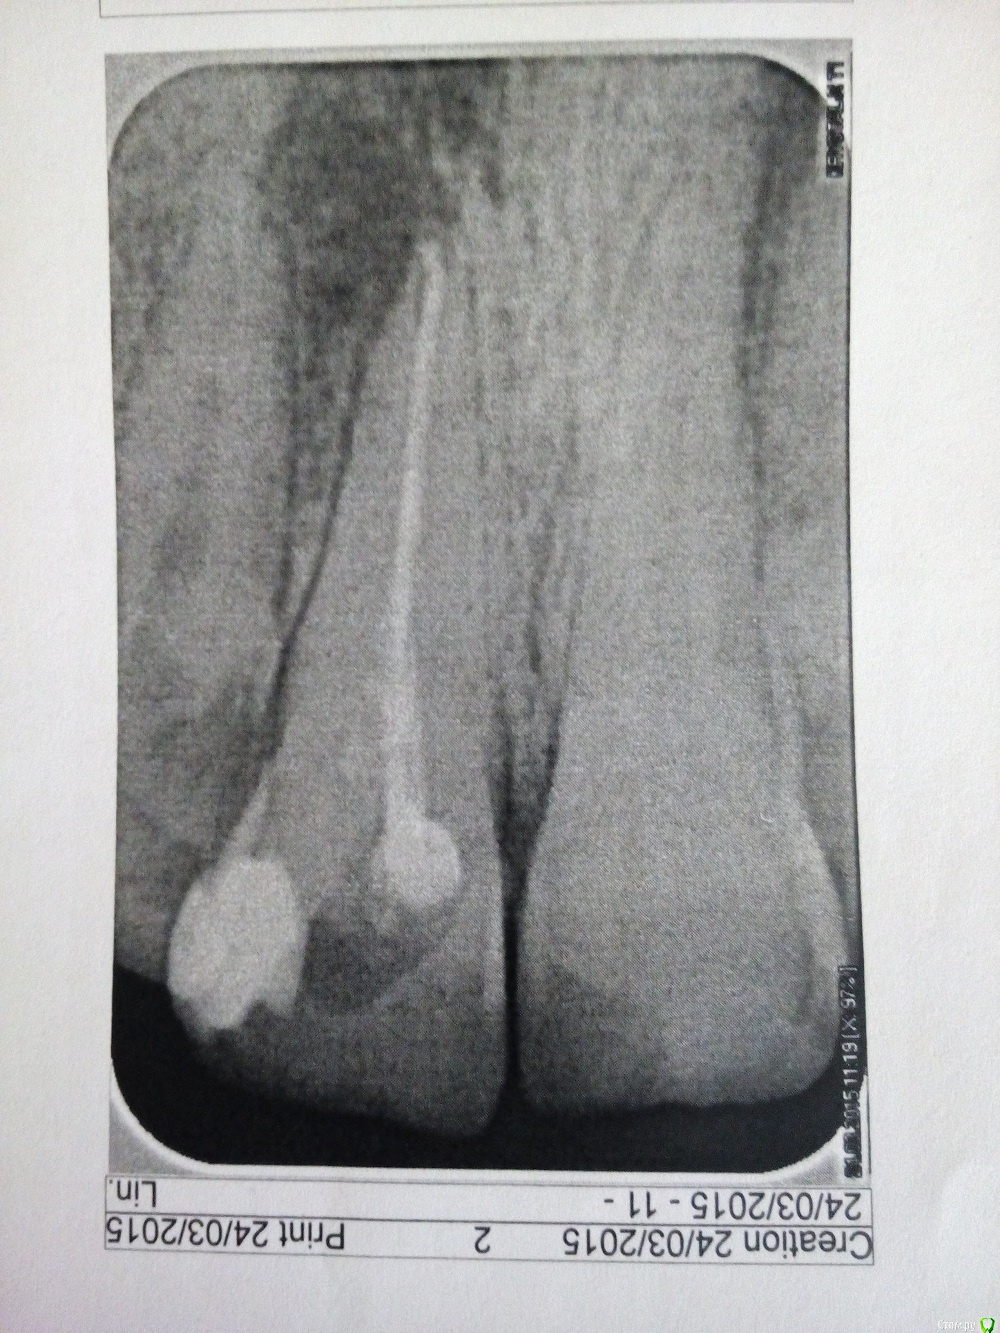

Игорьсан Опубликовано 24 марта, 2015 Поделиться Опубликовано 24 марта, 2015 Здравствуйте.Подскажите,этот зуб мне лечили почти год назад.Недавно он стал болеть,сходил к врачу,сделал снимок,говорит все нормально,что делать? Ссылка на комментарий

Игорьсан Опубликовано 25 марта, 2015 Автор Поделиться Опубликовано 25 марта, 2015 врач вскрыл пломбу и положил лекарство.сказал походить так неделю Ссылка на комментарий